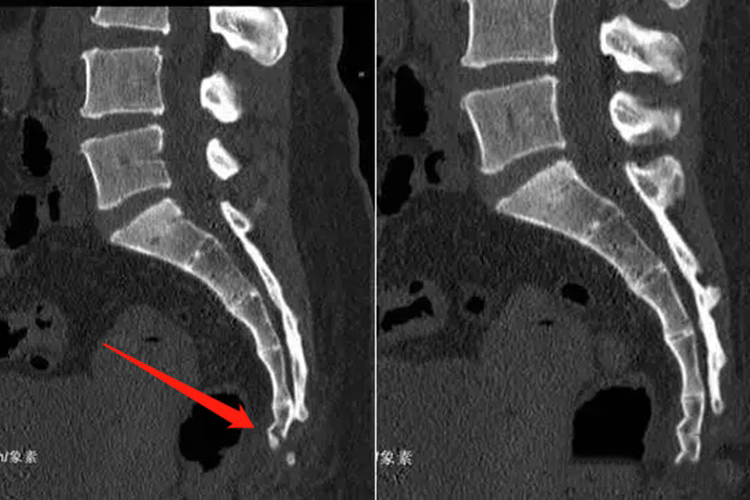

尾骨骨折

尾骨骨折后可见尾骨处向内凹陷,患者感觉局部疼痛,因疼痛加重而限制活动,严重者局部出现肿胀和肤色改变,甚至引起直肠破裂。